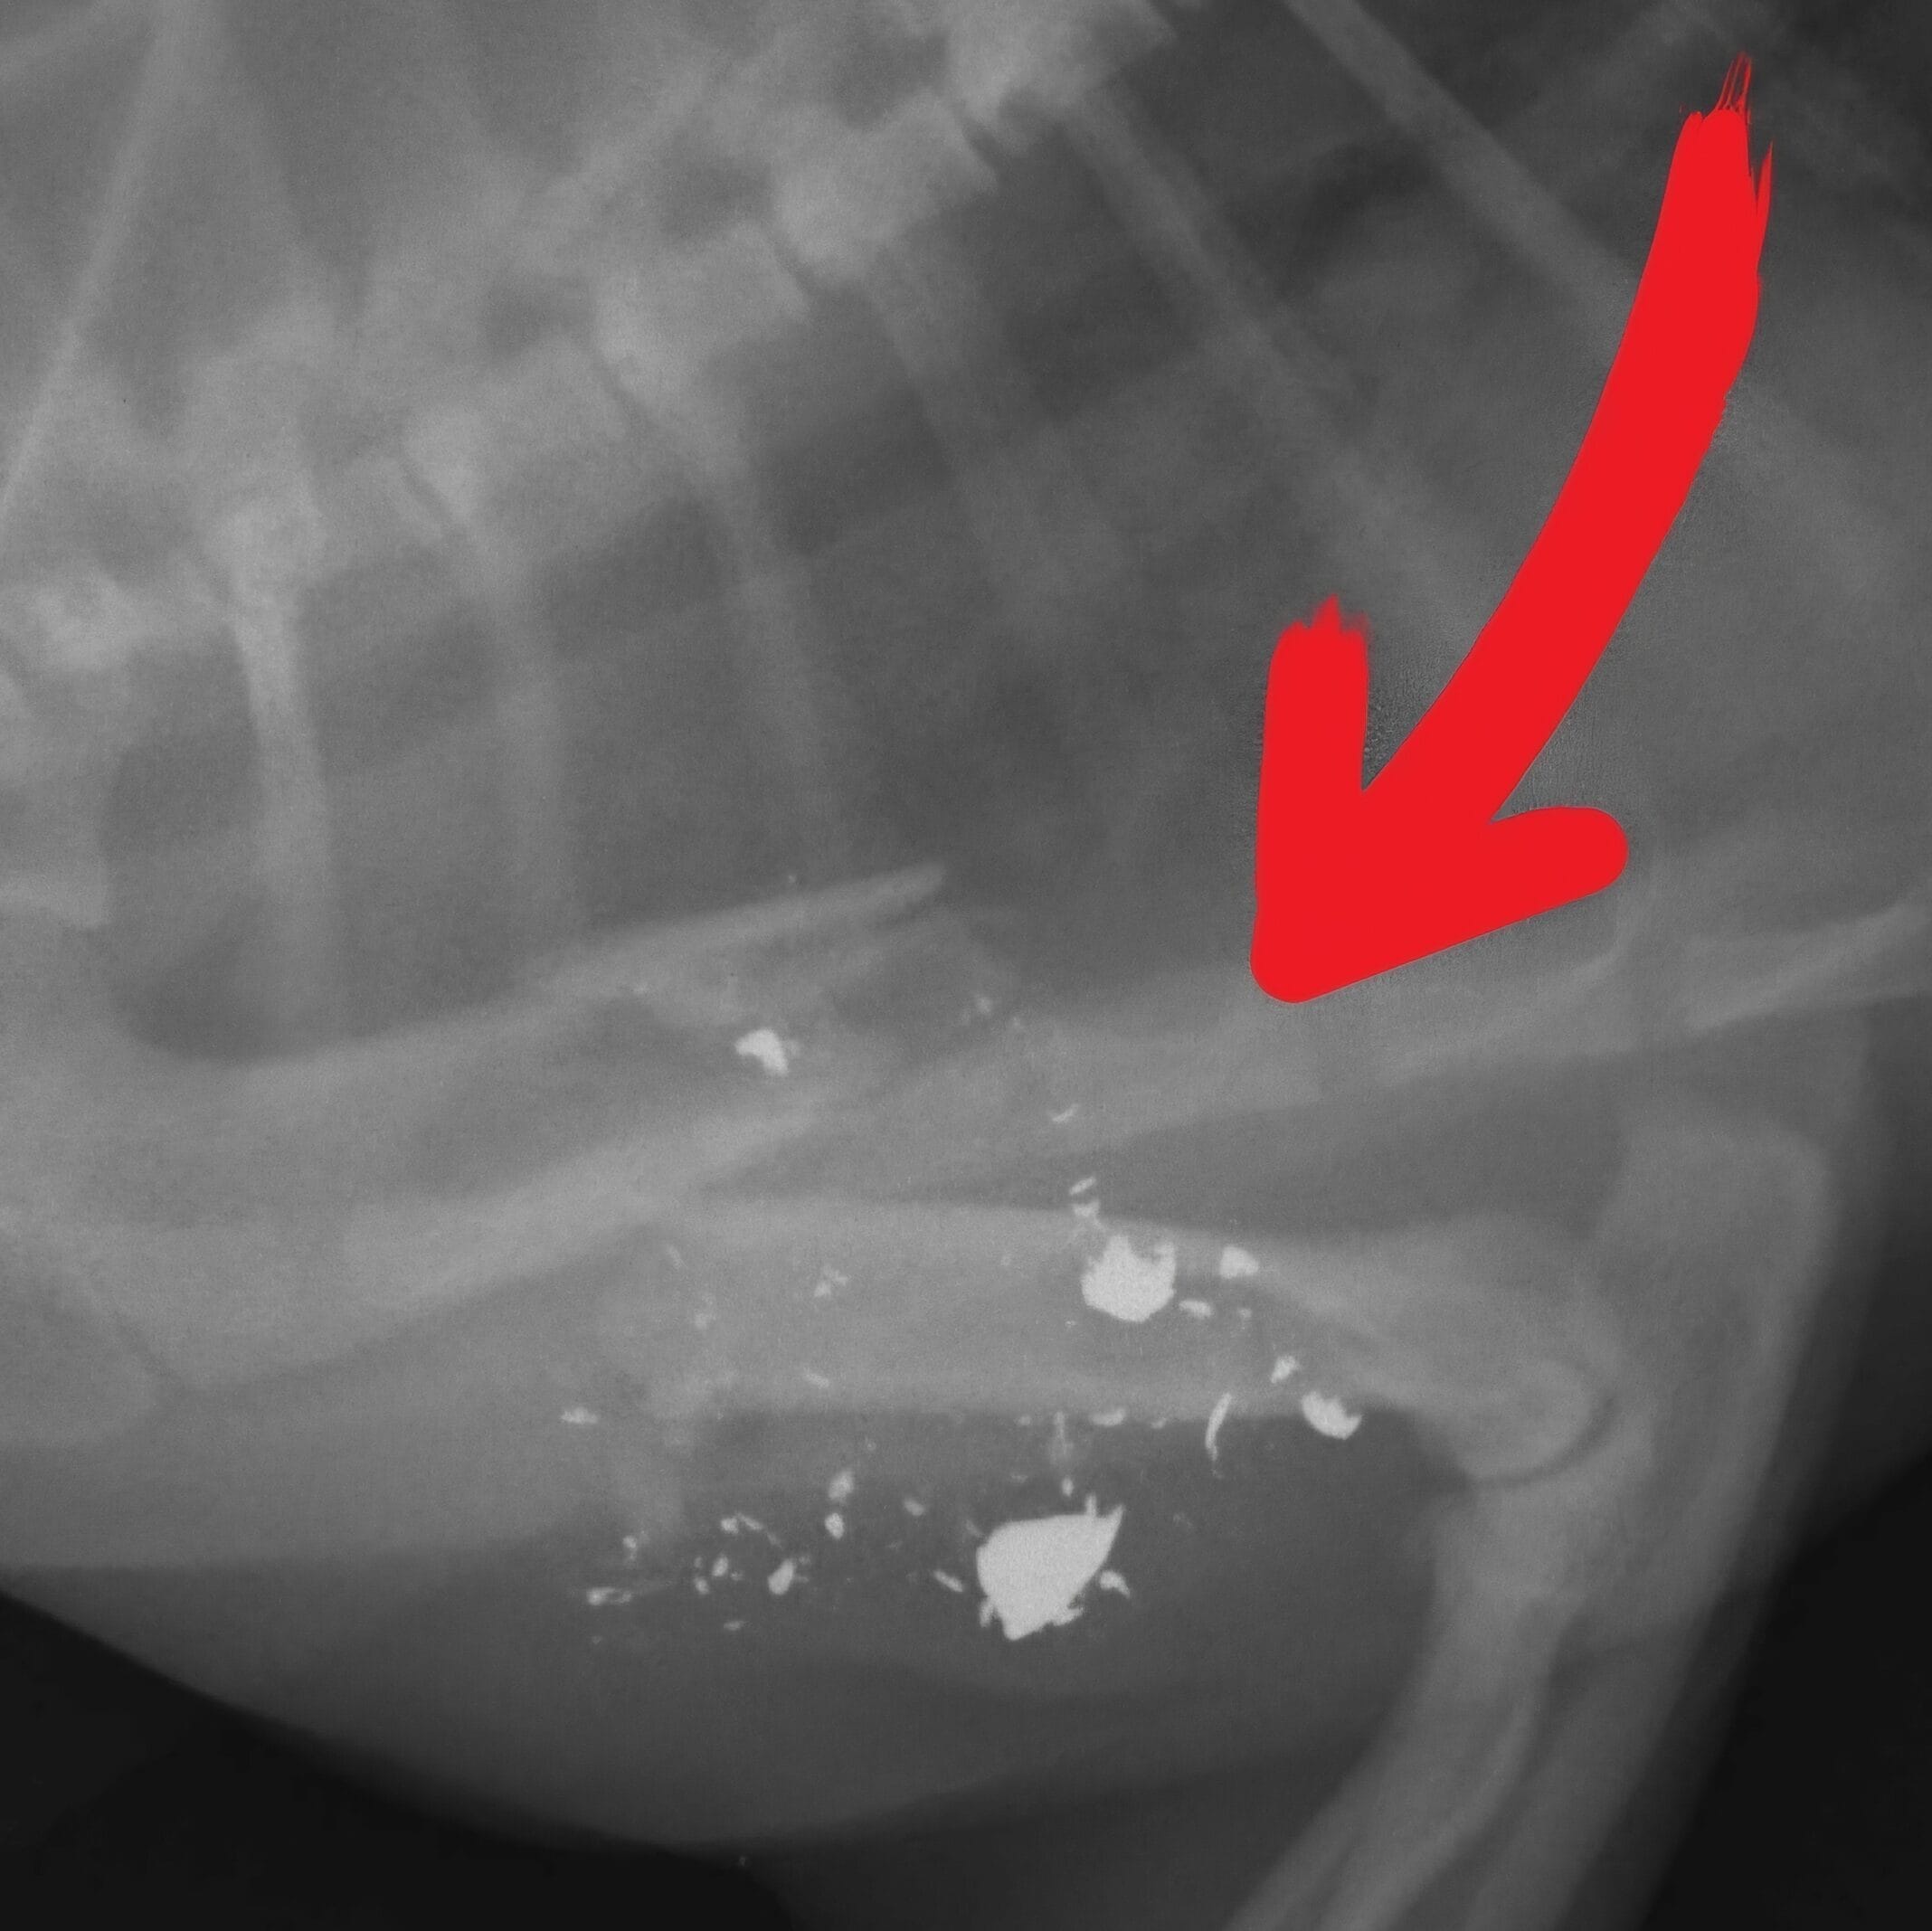

At first, everyone assumed he had been hit by a car. But when the X-rays came back, the truth was much worse.

Brewster had been shot.

The bullet had shattered his front leg, leaving him with a severe fracture and no one to care for him.